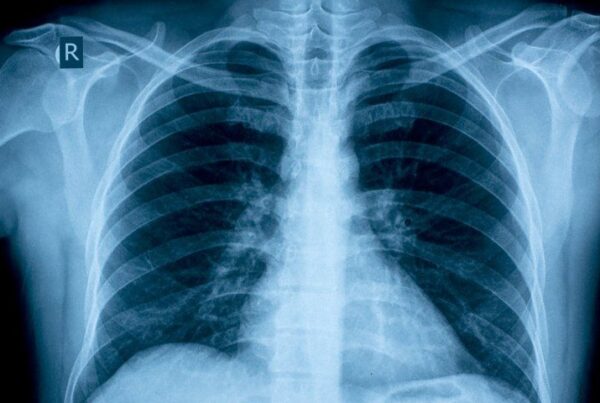

What are the effects of inhaling burned plant material on the lungs?

Whenever plant matter is burned, smoke is released, and with it potentially harmful particles. However, the largest population-based case-controlled study ever conducted of cannabis-only use yielded somewhat counter-intuitive results. For the 2,252 people observed in a Los Angeles, California, study, smoking (only) cannabis was found to be mildly lung-protective and was not associated with an increased risk of lung cancer.

Cannabis oil produces therapeutic effects in patients with chronic obstructive pulmonary disease (a serious lung disorder) and asthma. (See also the section on Lung Diseases in Chapter IV.) To minimize any potential risk of negative consequences to one’s lungs, some people use vaporizers to inhale cannabis rather than smoking cannabis wrapped in paper. Use of a vaporizer eliminates the inhalation of carbon compounds from burned paper. An infused oil or alcohol-based tincture can also be used to address symptoms related to lung disease.